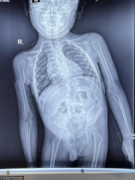

医“万”个为什么丨先天性脊柱侧弯选择手术好还是保守好?

【病急乱投医,拖延病情加重】 患者小小张,5岁,刚出生几个月就确诊患有先天性脊柱侧弯,父母心急如焚,四下求医,跑了各大医院终因年龄太小,又没有好的治疗方法,一直没有